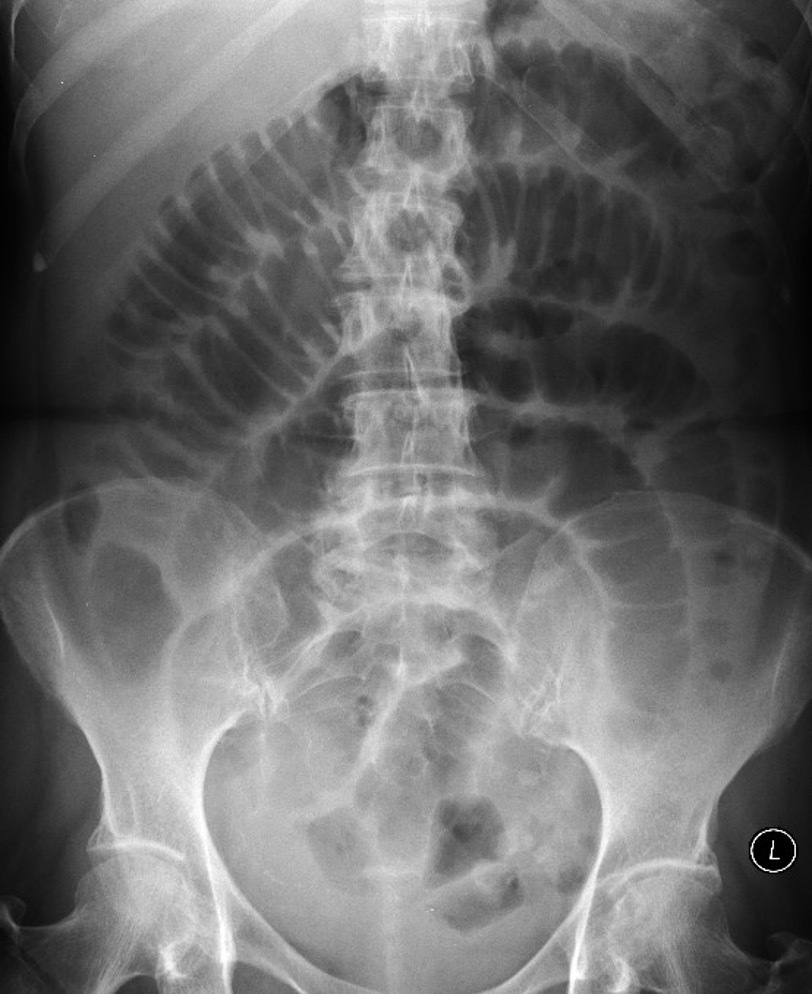

Sigmoid volvulus ## Footnote dilation causes the classic coffee-bean sign, a pathognomonic of sigmoid volvulus.

59